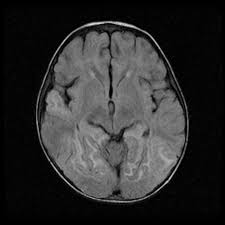

Lesions similar to cytotoxic edema, and lesions similar to vasogenic edema. Seizure, altered sensorium, fever frontal and temporal lobes, rarely extratemporal t2 hyperintensity, restricted diffusion, sometimes. Herpes encephalitis is the most common sporadic encephalitis in the united states and other industrialized countries .occurring as either a primary infection with herpes simplex virus or as a reactivation of latent virus, herpes encephalitis causes significant morbidity and mortality .early intervention with acyclovir significantly improves outcome; The clinical syndrome is often characterized by the rapid onset of fever, headache, seizures, focal neurologic signs, and impaired consciousness 1 . Having said that, mri with contrast is considered the most sensitive imaging modality, and findings are present in over half of individuals 8. The patients with the former type of lesions had fulminating disease, and were in severe clinical condition. Herpes simplex encephalitis occurs as 2 distinct entities: 4 it was found that, rather surprisingly, varicella zoster virus (vzv), the cause of chickenpox and herpes zoster, was the most frequently detected virus at 29%, with hsv and enteroviruses accounting for 11% of cases. Two subtypes are recognized which differ in demographics, virus, and pattern of involvement. (1)department of radiology, ankara numune education and research hospital, ankara, turkey. Neonatal herpes simplex encephalitis is caused by vertical transmission of infection during passage from birth canal with diffuse cerebral involvement within the first month after birth; As the older term limbic encephalitis implies, the most common location of involvement is the mesial temporal lobes and limbic systems, typically manifested by cortical thickening and increased t2/flair. In patients with herpes encephalitis, two distinct types of diffusion imaging findings (on b =1000 s/mm 2 images, and adc maps) were noted:

We present mri findings of two cases of herpes simplex encephalitis (hse) confirmed by pcr analysis, focusing on the serial changes after acyclovir therapy: 4 it was found that, rather surprisingly, varicella zoster virus (vzv), the cause of chickenpox and herpes zoster, was the most frequently detected virus at 29%, with hsv and enteroviruses accounting for 11% of cases. mri findings of herpes simplex encephalitis. For viral infection of the meninges, please refer to the general article on viral meningitis, and, for a broad view on the curriculum of infections of the central nervous system, refer to cns. The patients with the former type of lesions had fulminating disease, and were in severe clinical condition. The kappa value for interobserver agreement on rating the scans as normal or abnormal was good (0.65) for ct and moderate (0.59) for mri. Noguchi t, yoshiura t, hiwatashi a, et al. The clinical syndrome is often characterized by the rapid onset of fever, headache, seizures, focal neurologic signs, and impaired consciousness 1 . The patients with the former type of lesions had fulminating disease, and were in severe clinical condition. Specific diagnosis often requires pcr. As the older term limbic encephalitis implies, the most common location of involvement is the mesial temporal lobes and limbic systems, typically manifested by cortical thickening and increased t2/flair. In patients with herpes encephalitis, two distinct types of diffusion imaging findings (on b =1000 s/mm 2 images, and adc maps) were noted: A recent study in finland also used pcr to detect various viruses in the csf of over 3000 patients who had infections of the cns including encephalitis, meningitis, and myelitis.

(1)department of radiology, ankara numune education and research hospital, ankara, turkey. article in japanese yoshioka a, hirose g, tsukada k, oda r, kosoegawa h. Two subtypes are recognised which differ in demographics, virus, and pattern of involvement. Seizure, altered sensorium, fever frontal and temporal lobes, rarely extratemporal t2 hyperintensity, restricted diffusion, sometimes. Encephalopathy from herpes simplex encephalitis (hse). Specific diagnosis often requires pcr. Having said that, mri with contrast is considered the most sensitive imaging modality, and findings are present in over half of individuals 8. We present mri findings of two cases of herpes simplex encephalitis (hse) confirmed by pcr analysis, focusing on the serial changes after acyclovir therapy:

The patients with the former type of lesions had fulminating disease, and were in severe clinical condition. The diagnosis of hse is based on laboratory investigations, magnetic resonance (mr) imaging findings, electroencephalogram and, occasionally, a biopsy. Herpes encephalitis is the most common sporadic encephalitis in the united states and other industrialized countries .occurring as either a primary infection with herpes simplex virus or as a reactivation of latent virus, herpes encephalitis causes significant morbidity and mortality .early intervention with acyclovir significantly improves outcome; Herpes simplex (hsv) encephalitis is the most common cause of fatal sporadic fulminant necrotising viral encephalitis and has characteristic imaging findings. In patients with herpes encephalitis, two distinct types of diffusion imaging findings (on b =1000 s/mm 2 images, and adc maps) were noted: Relapse of encephalitis occurs in up to 10% of patients, manifested by recurrent symptoms, clinical and mri findings, and the presence of herpes simplex virus type 1 dna in the cerebrospinal fluid (csf). In children older than 3 months and in adults, hse is usually localized to the temporal and frontal lobes and is c. In patients with herpes encephalitis, two distinct types of diffusion imaging findings (on b =1000 s/mm 2 images, and adc maps) were noted: Herpes simplex (hsv) encephalitis is the most common cause of fatal sporadic fulminant necrotizing viral encephalitis and has characteristic imaging findings. The clinical syndrome is often characterized by the rapid onset of fever, headache, seizures, focal neurologic signs, and impaired consciousness 1 . We present mri findings of two cases of herpes simplex encephalitis (hse) confirmed by pcr analysis, focusing on the serial changes after acyclovir therapy: Two subtypes are recognised which differ in demographics, virus, and pattern of involvement. Despite advances in antiviral therapy over the past 2 decades, herpes simplex encephalitis (hse) remains a serious illness with significant risks of morbidity and death.